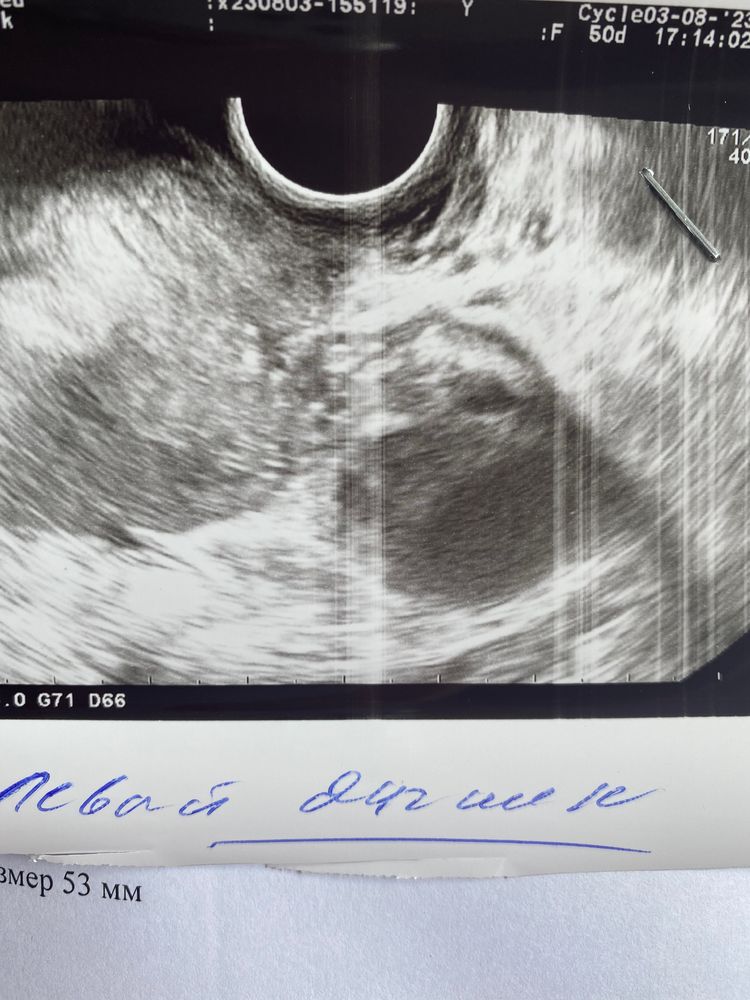

Позавчера было узи у моего гинеколога, эндометрий 9.7 доминантный фолликул 20 мм. После чего был укол хгч 10000. Позавчера! Пришла сегодня на узи ( тот же самый аппарат) другой узист (моя в отпуск ушла) она мне сказала, что ДФ=18 и эндометрий всего 6! Я могу предположить, что фолликул сдулся, но куда делся эндометрий? И кто-то понимает по картинкам, может, это ЖТ? А не фолликул? верхнее фото сегодня-нижнее позавчера

Мне кажется это жт.Без четкой контуры . Фолликул он та круглый аккуратный .Я сравниваю по своему узи просто )тоже была на стимуляции

Не верхнем подозреваю все таки формирование желтого тела!